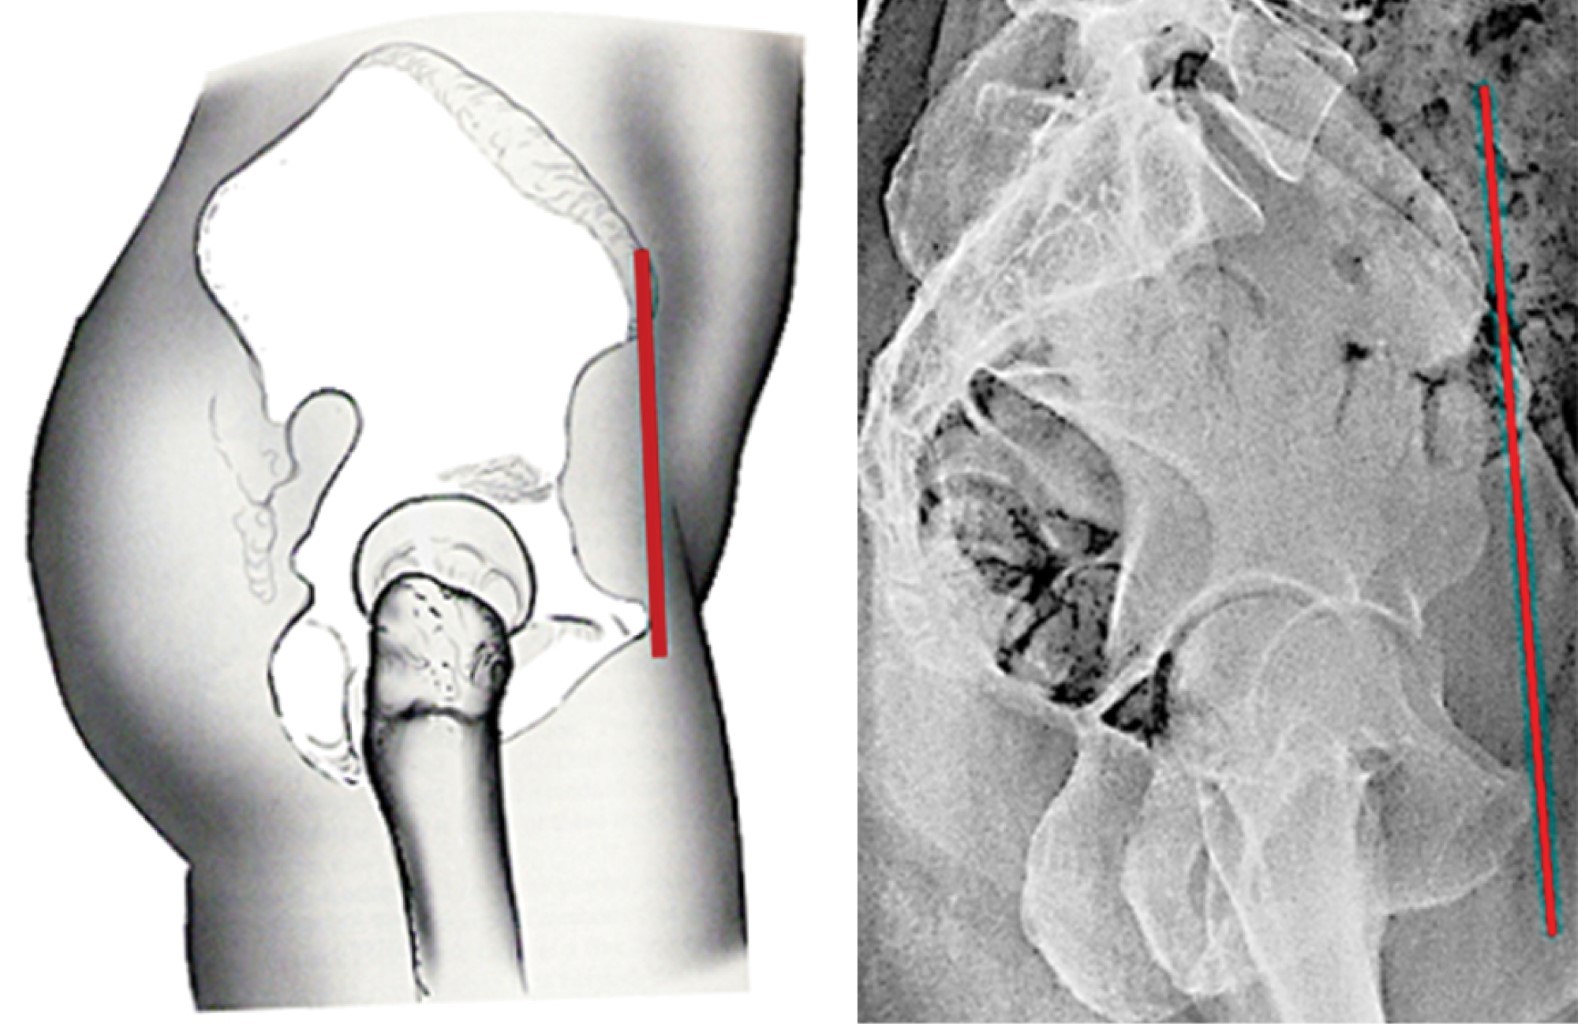

Es oportuno abrir aquí un paréntesis para definir qué es el "eje bicoxofemoral". Debido a que en una radiografía lateral es muy difícil hacer coincidir los centros de rotación de ambas cabezas femorales, se utiliza el concepto de "eje bicoxofemoral". Este eje se localiza en la parte media de una línea trazada entre los centros de rotación de ambas cabezas femorales en una radiografía lateral espino-pélvica (Figura 17).

Figura 16